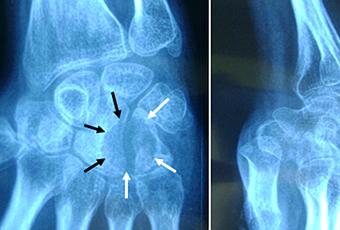

Nous rapportons ici le cas d’une jeune patiente âgée de 23 ans, étudiante, sans antécédents particuliers, qui a consulté pour impotence fonctionnelle et des douleurs du poignet droit, évoluant progressivement depuis six mois. Les douleurs étaient d’allure inflammatoire, elles sont exacerbées par la palpation d’une tuméfaction localisée au niveau de la face dorso-médiale du poignet qui est raide en inclinaison radiale (Figure 2). Toute tentative de mobilisation du poignet était extrêmement douloureuse. A la radiographie standard il existait une image ostéolytique bien circonscrite au niveau de l’hamatum mordant sur Le bord médial du capitatum (Figure 3). Le scanner a mis en évidence une lésion lytique occupant la quasi-totalité de l’hamatum avec lyse du bord médiale du capitatum, respectant les parties molles (Figure 4).